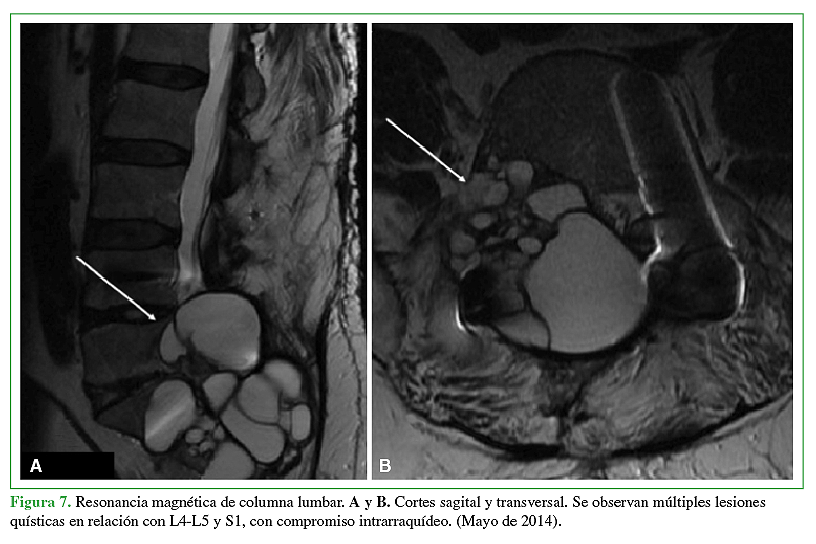

La hidatidosis es una enfermedad causada por el estado larval del platelminto Echinococcus, siendo la especie más prevalente Echinococcus granulosus. Es endémica Eurasia, Africa, Australia y Sudamérica. En Chile tiene una incidencia notificada de 2,1 casos por 100.000 habitantes y a pesar de que está asociada a las zonas ganaderas del sur de Chile, se presenta a lo largo de todo el territorio debido al desplazamiento de la población y su largo período de incubación. Se caracteriza por la presencia de un quiste habitualmente a nivel hepático (75%) o pulmonar (15%). La afectación de otros territorios es menos frecuente y el compromiso óseo es una rareza que no supera el 1 a 2,5%, ya sea en el tejido trabecular o canal medular. El tratamiento por lo general es médico-quirúrgico con resultados clínicos dispares debido a alta tasa de recurrencias y secuelas. La experiencia en el manejo de pacientes afectados con hidatidosis intrarraquídea es limitada debido a su baja frecuencia. Por ello quisimos reportar 2 casos observados en nuestro centro y analizar su manejo.Descargas